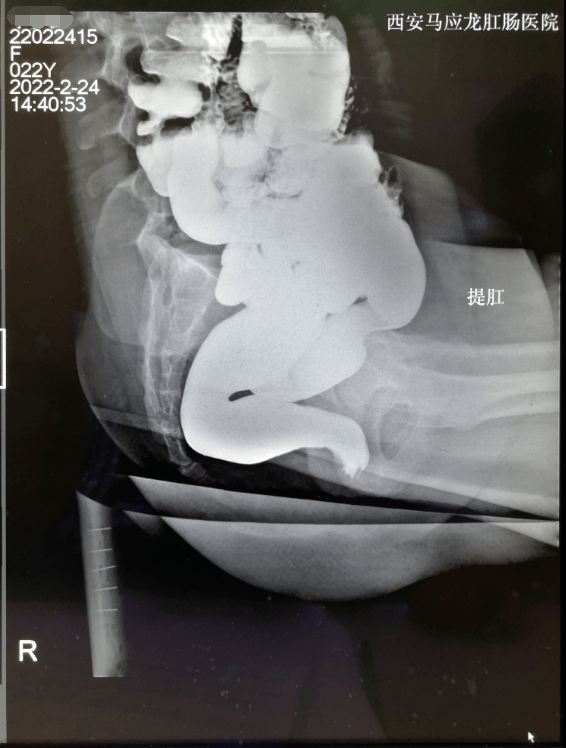

患者排粪造影检查结果 -------------------- 此消息发自android

图片尺寸2448x3264

从排粪造影看产后出口梗阻型便秘 - 好大夫在线